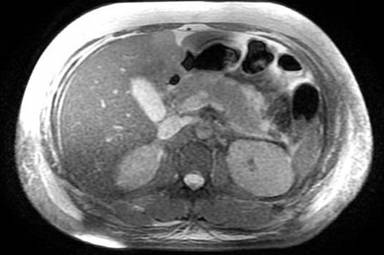

Figure 2. MRCP showing findings of thickened, heterogeneous appearance to the pancreas with adjacent fluid at the tail and body suggestive of acute pancreatitis. |